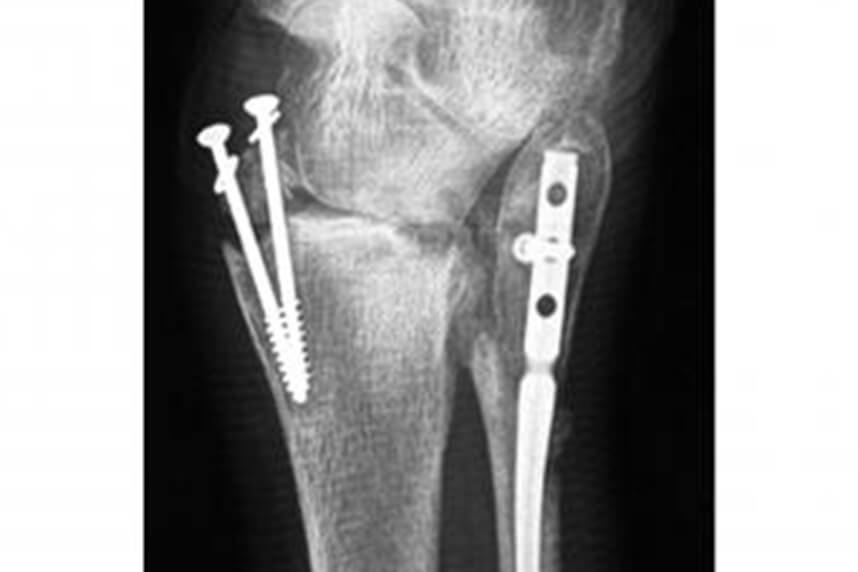

Fracturile maleolare

Acestea sunt cele mai frecvente fracturi ale membrului inferior: ele implica maleolele interne si externe, uneori imbinate prin leziuni ale ligamentelor gleznei. Fractura care implica cel putin doua maleole si partea posterioara a tibiei este definita ca o fractura tri-maleolara.

Probabil ai suferit o trauma in urma unui accident de masina, un traumatism cauzat in timpul unei activitati sportive sau a unei caderi accidentale. In functie de diferitele tipuri de fractura, exista diverse tratamente chirurgicale la care sa fii supus.

Numeroase substitute osoase sintetice sunt folosite la fel de bine ca niste fixatoare externe. Veti fi capabil sa incepeti reabilitarea dupa o anumita perioada de mobilizare cu un plasture sau fixator. Este important sa stiti ca reabilitarea propusa pentru acest tip de patologie este una pe termen lung si provocatoare, necesitand in medie patru luni, pentru realizarea unei recuperari discrete a functionalitatii si aproximativ opt luni pentru revenirea la activitatea sportiva. In general, inlocuitorii ososi sintetici sunt indepartati la un an dupa interventia chirurgicala. Reabilitarea dupa indepartarea lor va dura aproape o luna.